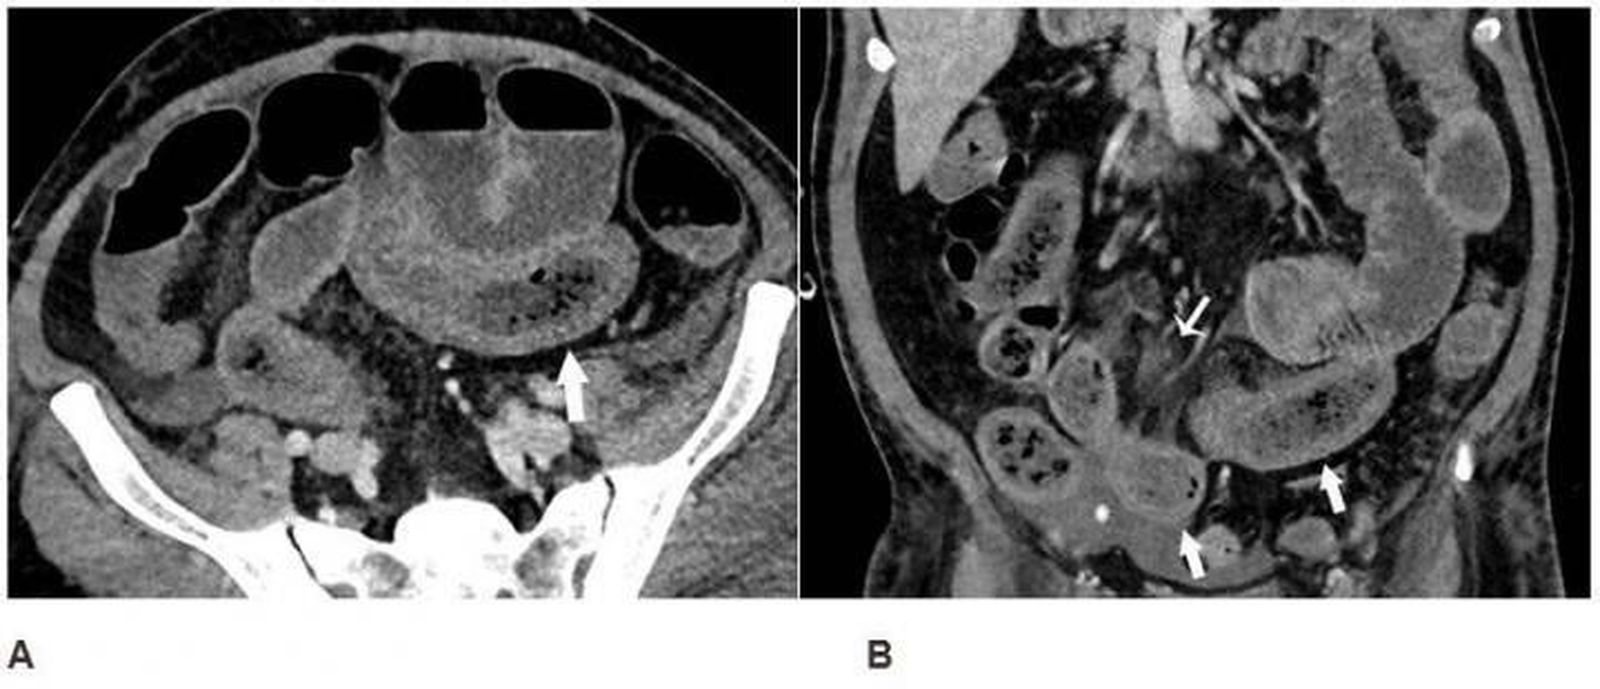

Anormalidades en el intestino de los pacientes con Covid-19

Se observaron anormalidades intestinales en el 31 por ciento de las tomografías computarizadas (3,2% de todos los pacientes) y fueron más frecuentes en pacientes ingresados en una Unidad de Cuidados Intensivos (UCI) que en otros pacientes hospitalizados. Los hallazgos intestinales incluyeron engrosamiento y hallazgos de isquemia tales como neumatosis (gas en la pared intestinal).

"Encontramos anormalidades intestinales en las imágenes en pacientes con Covid-19, especialmente en pacientes más graves ingresados en una UCI", han explicado los investigadores, quienes han informado de que la isquemia intestinal en algunos pacientes puede estar causada por coágulos sanguíneos pequeños.

"Los pacientes en la UCI pueden tener isquemia intestinal por otros motivos, pero sabemos que el Covid-19 puede provocar coagulación y lesiones en los vasos pequeños, por lo que el intestino también podría verse afectado por este virus", han apostillado los científico.